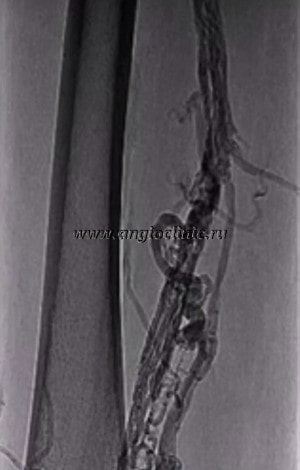

флебографический снимок при варикозе вен голени

Исследование вен нижних конечностей с контрастом показано при необходимости подтвердить диагноз, если с помощью функциональных проб и/или УЗИ сосудов получены сомнительные результаты. Обычно флебография используется нечасто, а только в случаях, которые действительно вызывают сомнения у врача в плане диагностики. Предполагаемые заболевания при этом таковы:

- Тромбоз глубоких вен голени и бедра,

- Варикозная болезнь нижних конечностей (комплексно оценивается функция клапанного аппарата поверхностных и глубоких вен),

- Врожденные аномалии строения венозных сосудов,

- Предполагаемое использование вены в качестве шунта, например, при аорто-коронарном шунтировании.